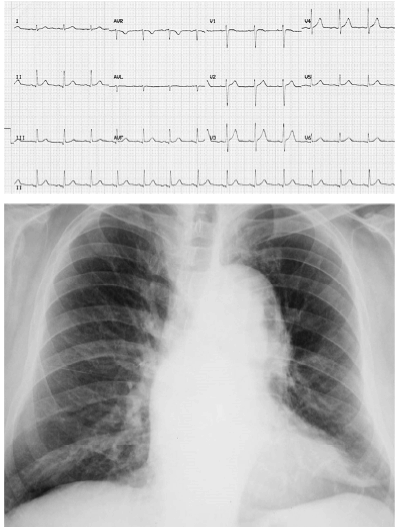

Um indivíduo de 32 anos de idade relatava dor torácica lancinante na parede anterior com irradiação para o dorso, de forte intensidade e sem alívio com analgésicos comuns havia seis horas. Ele possui antecedentes de subluxação do cristalino e ectasia dural lombosacral. Ao exame físico, encontrava-se sudorético e acianótico, com pressão arterial de 198 × 122 mm/Hg e frequência cardíaca de 92 bpm. Apresentava: pectus carinatum, ritmo cardíaco regular em dois tempos com sopro diastólico (++/4) no segundo espaço intercostal à direita, além de pulsos reduzidos em membros inferiores. O resultado da troponina ultrassensível e os exames laboratoriais de rotina foram normais. Realizou um eletrocardiograma e uma radiografia de tórax, que são mostrados a seguir.

Assinale a opção que corresponde a mais provável condição associada ao caso clínico apresentado no texto 18A03-III.

Diante do caso apresentado pelo texto 18A03-III, assinale a opção que corresponde à conduta imediata mais apropriada para o controle dos níveis pressóricos.